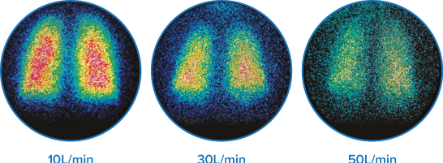

Imágenes de gammagrafía representativas del depósito pulmonar con diferentes flujos a 10, 30 y 50 l/min en adultos sanos.† 6

- entre un 3,5 % y un 17 % de medicación administrada a los pulmones dependiendo de los flujos†6

- Respuesta broncodilatadora eficaz, incluso con un flujo de gas de 50 l/min‡10